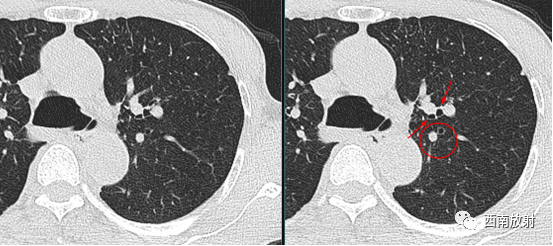

判断支气管扩张症的 MSCT表现,依据病变的程度、走行方向扫描层面有一定的关系。而印戒征和轨道征见于柱状支气管扩张,正常支气管管径稍小于伴行的肺动脉, 若支气管管径大于伴行的肺动脉直径,且此时的走行方向与扫描图像层面垂直,即构成特征性的印戒征。

▲图:支气管扩张,印戒征,支气管扩张旁边伴随肺动脉影。